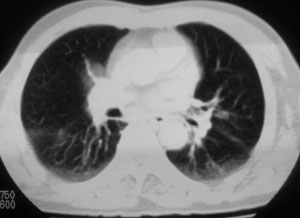

性别 男  62岁 因咳嗽及左肱骨剧烈痛疼数天来院检查。

右中央型肺癌并肱骨转移。

考虑右肺中叶肺癌并左肱骨转移伴病理性骨折。

支持右肺中心型肺癌并肺内及左肱骨转移伴病理性骨折

右肺中心型肺癌并中叶不张,左肱骨溶骨性转移并病理骨折。